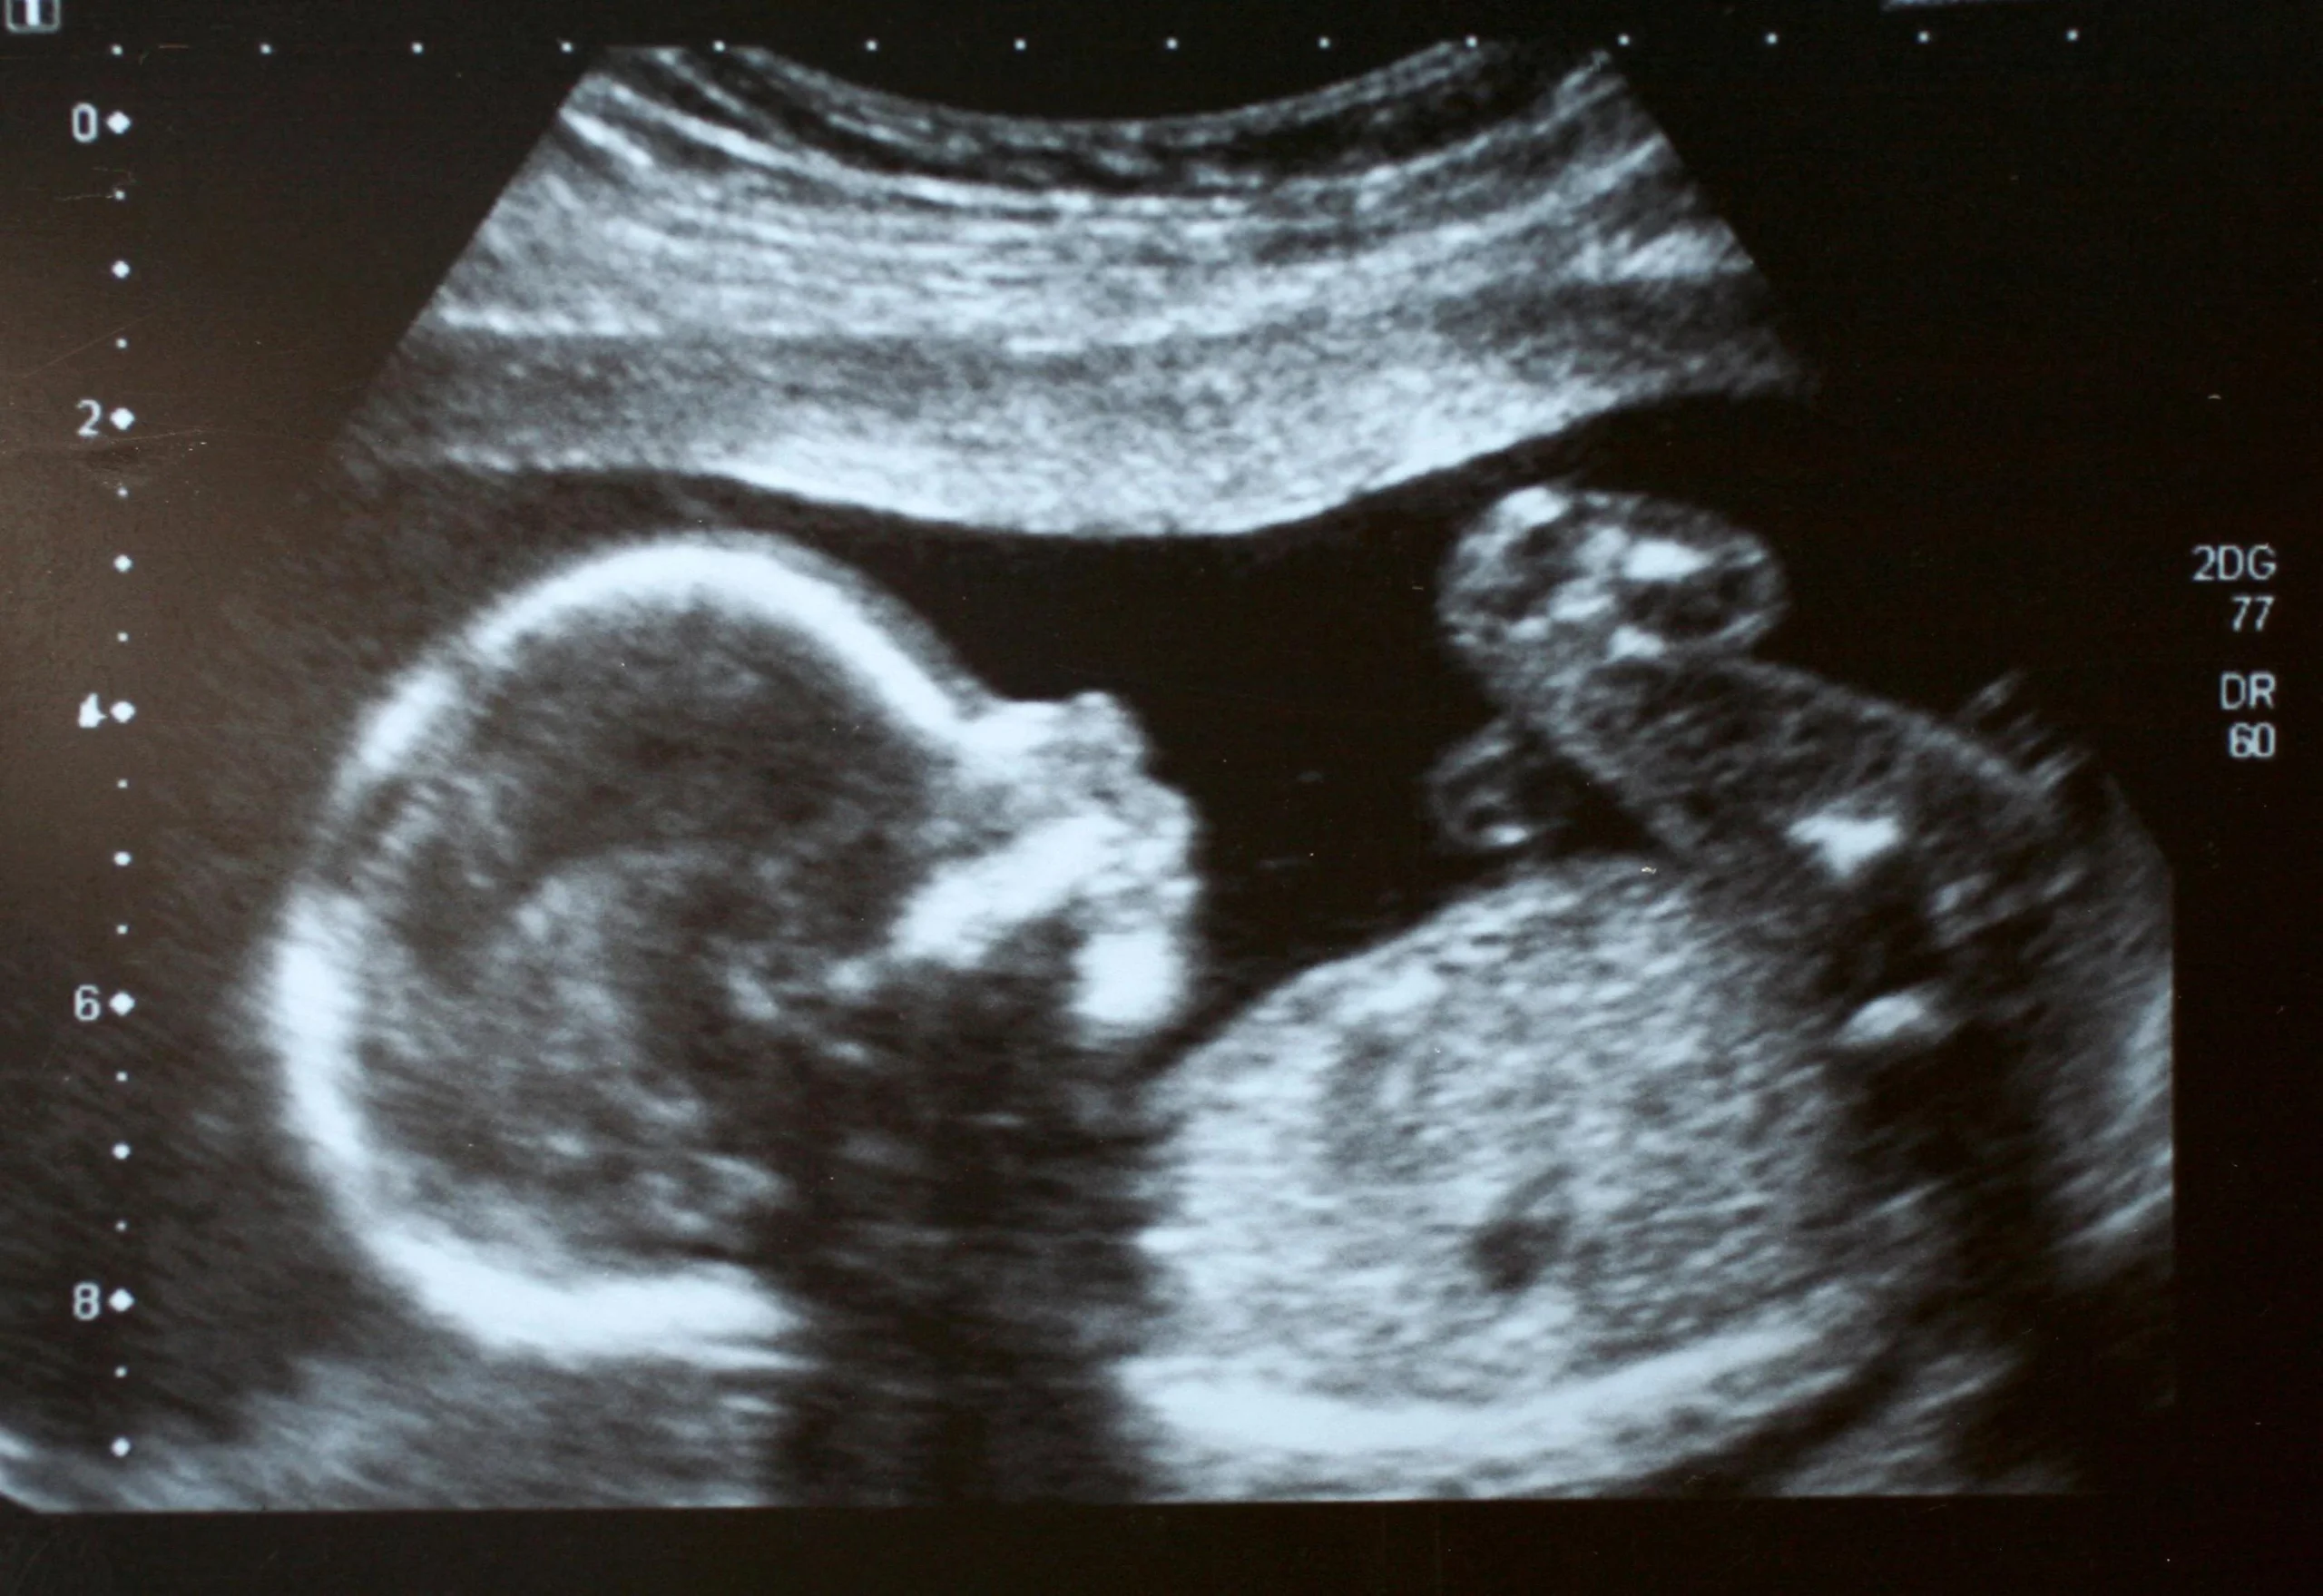

Schwangerschaft Ultraschalluntersuchungen sind ein sicheres und schmerzloses Verfahren, das mithilfe von Schallwellen ein Bild des ungeborenen Kindes und der Gebärmutter erzeugt. Diese Bilder ermöglichen es dem Arzt, die Entwicklung des Kindes zu beobachten, seine Größe und Position zu bestimmen, den Herzschlag zu hören und die Plazenta zu beurteilen. Darüber hinaus können Ultraschalluntersuchungen helfen, potenzielle Komplikationen wie z. B. Mehrlingsschwangerschaften, Fehlbildungen, Nabelschnurprobleme oder eine unzureichende Fruchtwassermenge frühzeitig zu erkennen.

- 3D-Ultraschalluntersuchung: Diese Art der Untersuchung erzeugt ein dreidimensionales Bild des ungeborenen Kindes. Dies ermöglicht es den Eltern, die Gesichtszüge und andere Merkmale ihres Babys zu sehen, und kann für die Diagnose von Fehlbildungen hilfreich sein.

- 4D-Ultraschalluntersuchung: Diese Untersuchung erzeugt ein dreidimensionales, bewegtes Bild des ungeborenen Kindes. Es ermöglicht den Eltern, das Baby im Mutterleib zu beobachten und zu sehen, wie es sich bewegt.

Eine Ultraschalluntersuchung ist ein schmerzloses und nicht-invasives Verfahren. Die Schwangere liegt auf einem Untersuchungstisch, und der Arzt oder die Ärztin trägt ein Gel auf den Bauch oder die Vagina auf. Dieses Gel hilft, die Schallwellen besser zu leiten. Der Arzt führt dann den Schallkopf über den Bauch oder in die Vagina und bewegt ihn vorsichtig, um ein Bild des ungeborenen Kindes und der Gebärmutter zu erzeugen. Die Bilder werden auf einem Bildschirm angezeigt, den der Arzt oder die Ärztin interpretieren kann.